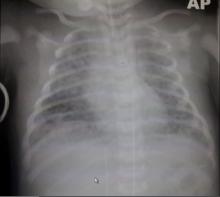

In this video, the authors show how to start veno-arterial ECMO support (VA-ECMO) through cervical cannulation, using the right internal jugular vein and right common carotid artery. This site is chosen over the femoral approach, as it avoids the associated complications, particularly in newborns and non-walking infants. In patients who require ECMO after a cardiac operation, an initial transthoracic approach is established. Cervical cannulation is a method to move the cannulas away from the chest, and to allow delayed chest closure in such patients, while continuing ECMO support. Cervical cannulation can be performed at the bedside, in an emergency setting, and during cardiac massage.